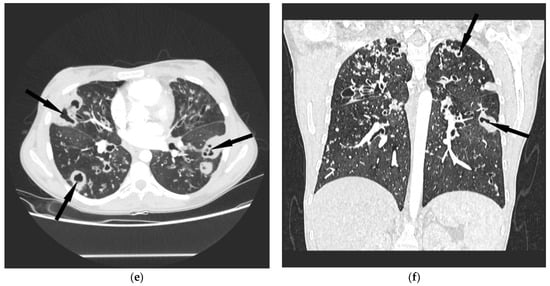

4.3. Radiological Data